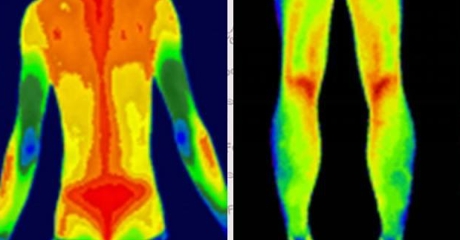

紅外熱像儀利用紅外輻射技術(shù),將物體散發(fā)的紅外輻射轉(zhuǎn)化為可見的熱圖。熱圖通過不同顏色的色彩表示不同的溫度區(qū)域,從而幫助我們觀察和分析物體表面的溫度分布情況。

- 溫度對比:通過觀察熱圖中不同區(qū)域的顏色差異,可以比較不同區(qū)域的溫度差異。高溫區(qū)域通常呈現(xiàn)為亮色或暖色調(diào),低溫區(qū)域則為暗色或冷色調(diào)。通過對比不同區(qū)域的溫度差異,我們可以快速發(fā)現(xiàn)異常情況。

- 熱點(diǎn)定位:熱圖中的亮色區(qū)域通常表示溫度較高的區(qū)域,這些區(qū)域可能存在潛在的問題或異常。通過定位和標(biāo)記熱圖中的熱點(diǎn),我們可以進(jìn)一步分析這些區(qū)域的原因和可能的解決方案。

三、色彩和溫度的對應(yīng)關(guān)系

熱圖中的色彩用于表示不同溫度區(qū)域,不同的紅外熱像儀廠商可能會(huì)采用不同的配色方案。一般而言,常見的配色方案有彩虹色、鐵紅色和黑白色等。下面是一個(gè)常見的色溫對應(yīng)關(guān)系表格,供您參考:

| 色彩 | 溫度范圍 |

| 紅色 | 高溫區(qū)域 |

| 橙色 | |

| 黃色 | |

| 綠色 | 中溫區(qū)域 |

| 藍(lán)色 | |

| 青色 | |

| 紫色 | 低溫區(qū)域 |

請注意,不同紅外熱像儀的配色方案可能略有不同,因此在具體應(yīng)用中,需要結(jié)合設(shè)備說明書來理解和解讀熱圖。